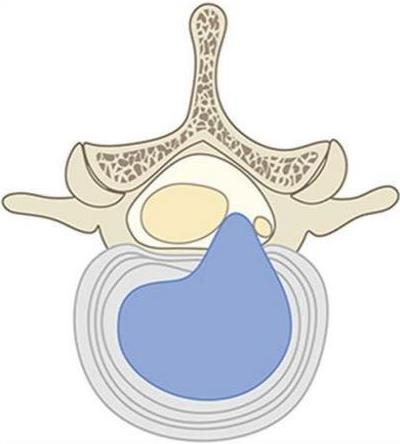

• 不同入路脊柱内镜手术治疗L4/5节段脱垂型腰椎间盘突出症的疗效比较

摘要:目的 观察经椎间孔入路内镜下腰椎间盘切除术(TELD)和经椎板间入路内镜下腰椎间盘摘除术(IELD)治疗L4/5节段脱垂型腰椎间盘突出症(LDH)的临床疗效。方法 回顾性分析2020年11月-2022年11月该院采用脊柱内镜手术治疗的75例L4/5节段脱垂型LDH患者的临床资料。根据手术入路的不同,将患者分为TELD组(53例)和IELD组(22例)。比较两组患者的手术情况和术后疗效。结果 与TELD组比较,IELD组的手术时间明显缩短,术中透视次数明显减少,差异均有统计学意义(P < 0.05);两组患者住院时间和并发症发生率比较,差异均无统计学意义(P > 0.05)。所有患者术后均获得12~19个月的随访。两组患者末次随访时的视觉模拟评分法(VAS)评分和Oswestry功能障碍指数(ODI)明显低于术前,且IELD组明显低于TELD组,差异均有统计学意义(P < 0.05)。按照突出物和神经根的不同位置进一步分析,两组肩上型患者(TELD组10例,IELD组6例)末次随访时的VAS评分和ODI明显低于术前,且IELD组末次随访时的VAS评分明显低于TELD组,差异均有统计学意义(P < 0.05);两组腋下型患者(TELD组8例,IELD组16例)末次随访时的VAS评分和ODI明显低于术前,且IELD组明显低于TELD组,差异均有统计学意义(P < 0.05);35例肩前型患者经TELD术后,末次随访时的VAS评分和ODI明显低于术前,差异有统计学意义(P < 0.05)。按照突出物的不同Lee分区进一步分析,两组Lee Ⅲ区患者(TELD组44例,IELD组10例)末次随访时的VAS评分和ODI明显低于术前,且IELD组的ODI明显低于TELD组,差异均有统计学意义(P < 0.05);两组Lee Ⅳ区患者(TELD组9例,IELD组12例)末次随访时的VAS评分和ODI明显低于术前,且IELD组明显低于TELD组,差异均有统计学意义(P < 0.05)。结论 采用TELD和IELD治疗L4/5节段脱垂型LDH,均可获得较满意的减压效果,但IELD的手术时间相对较短,X线透视次数较少,且对肩上型、腋下型、Lee Ⅲ区和Lee Ⅳ区的减压效果更有优势。